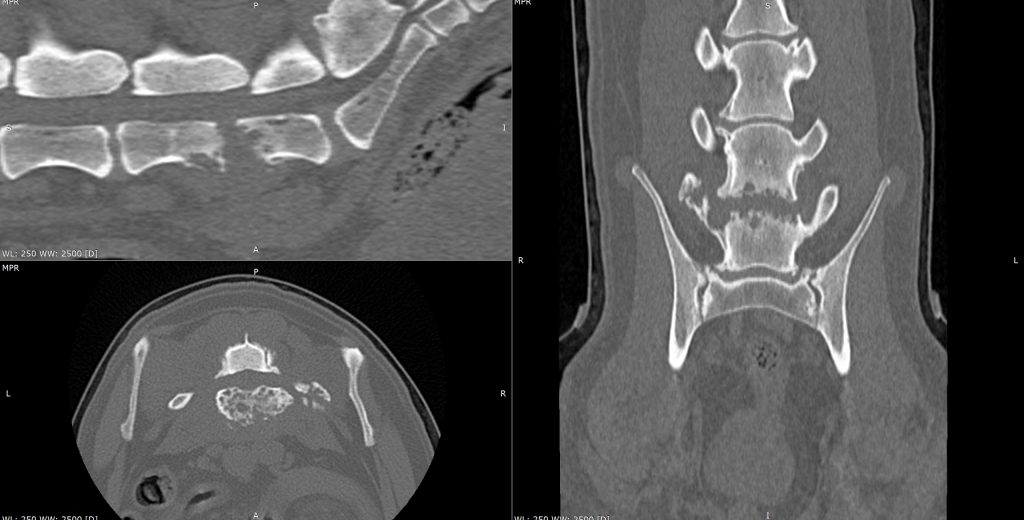

Le scanner excelle dans l’analyse des structures osseuses. Il est l’examen de référence pour l’étude des fractures complexes, des fractures comminutives, des fissures non visibles à la radiographie, des atteintes articulaires associées et des remaniements osseux fins.

• En orthopédie, il permet une analyse détaillée des articulations, notamment du coude, de l’épaule, du carpe, du tarse, du genou et de la hanche. Il est particulièrement utile pour l’exploration des dysplasies, des incongruences articulaires, des lésions ostéochondrales et des complications postopératoires.

• En traumatologie, le scanner est devenu indispensable. Il permet d’évaluer avec précision l’étendue des lésions, le nombre et la taille des fragments osseux, l’atteinte des surfaces articulaires et les relations avec les tissus environnants. Ces informations conditionnent directement la stratégie chirurgicale et le pronostic fonctionnel.